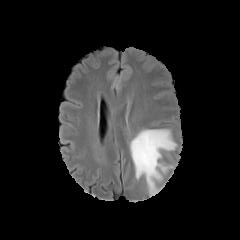

We observe that the generated normal-looking from ANT-GAN can also be used to directly segment the image, since the only difference between a synthesized normal-looking image and its real abnormal counterpart is region with the lesion. To illustrate this, we calculate the absolute difference between x𝑥x and 𝒢A2N(x)subscript𝒢A2N𝑥\mathcal{G}_{\rm{A2N}}(x) and show the segmentation after binary thresholding at 0.1 in Figure 9.

Refer to caption

(a) Tumor x𝑥x

(b) 𝒢A2N(x)subscript𝒢A2N𝑥\mathcal{G}_{\rm{A2N}}(x)

(c) Prediction

(d) Label

Figure 9: Example segmentation obtained by taking the absolute difference between the real tumor MRI x𝑥x and the generated normal-looking MRI 𝒢A2N(x)subscript𝒢A2N𝑥\mathcal{G}_{\rm{A2N}}(x), after binarization at a preset threshold.